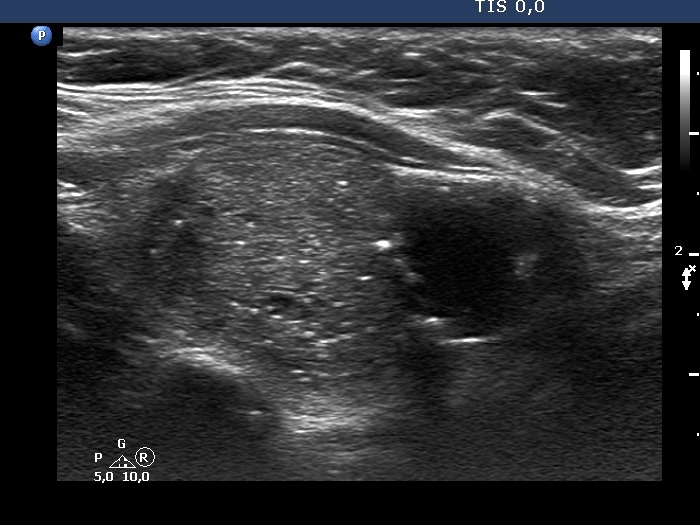

Second examination 7 years later (second and third rows of images):

Ultrasonography. The presentation remained unchanged. Using a better ultrasound device, it turned out that the echogenic granules are related to ventral cystic areas. Therefore, these are not microcalcifications, but figures caused by back wall cystic enhancement.Suggestion: yearly TSH determination, ultrasound in 4 years.

- The interpretation of the discrete lesions in the left lobe is difficult. I mean that this is a dominantly solitary nodule with a peripheral-type cystic portion. (See the explanation at the images.)